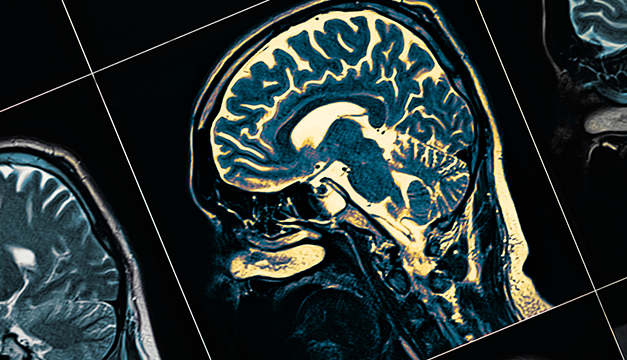

El doctor Arturo Ayala Arcipreste, encargado del servicio de neurocirugía del Hospital Juárez de México, explicó este lunes en entrevista con Efe que, si bien el virus afecta principalmente al sistema respiratorio, su mecanismo de afección incluye otras áreas como el cerebro.

Esto sucede, detalló, porque este es el tejido del cuerpo que consume casi el 20 % del oxígeno que respira el ser humano "y si tenemos un problema ventilatorio que afecta la adecuada oxigenación, el cerebro se va a afectar".

El especialista explicó que el coronavirus puede provocar que la circulación sanguínea se vea afectada precisamente por esta falta de oxigenación, lo que provoca que se formen coágulos y, en aproximadamente el 80 % de los casos graves en donde se presenta el infarto cerebral, deriva en la muerte.

Esta reacción del organismo, explicó el neurólogo, puede provocar daños en el sistema nervioso central y provocar daños neurológicos que tengan secuelas irreversibles.